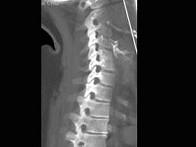

问题 男,35岁,反复颈部不适20余年,结合图像,最可能的诊断是?(?)

选项 A.颈椎椎体融合 B.颈椎结核 C.颈椎退行性变 D.颈椎压缩性骨折 E.颈椎骨转移瘤

答案 A